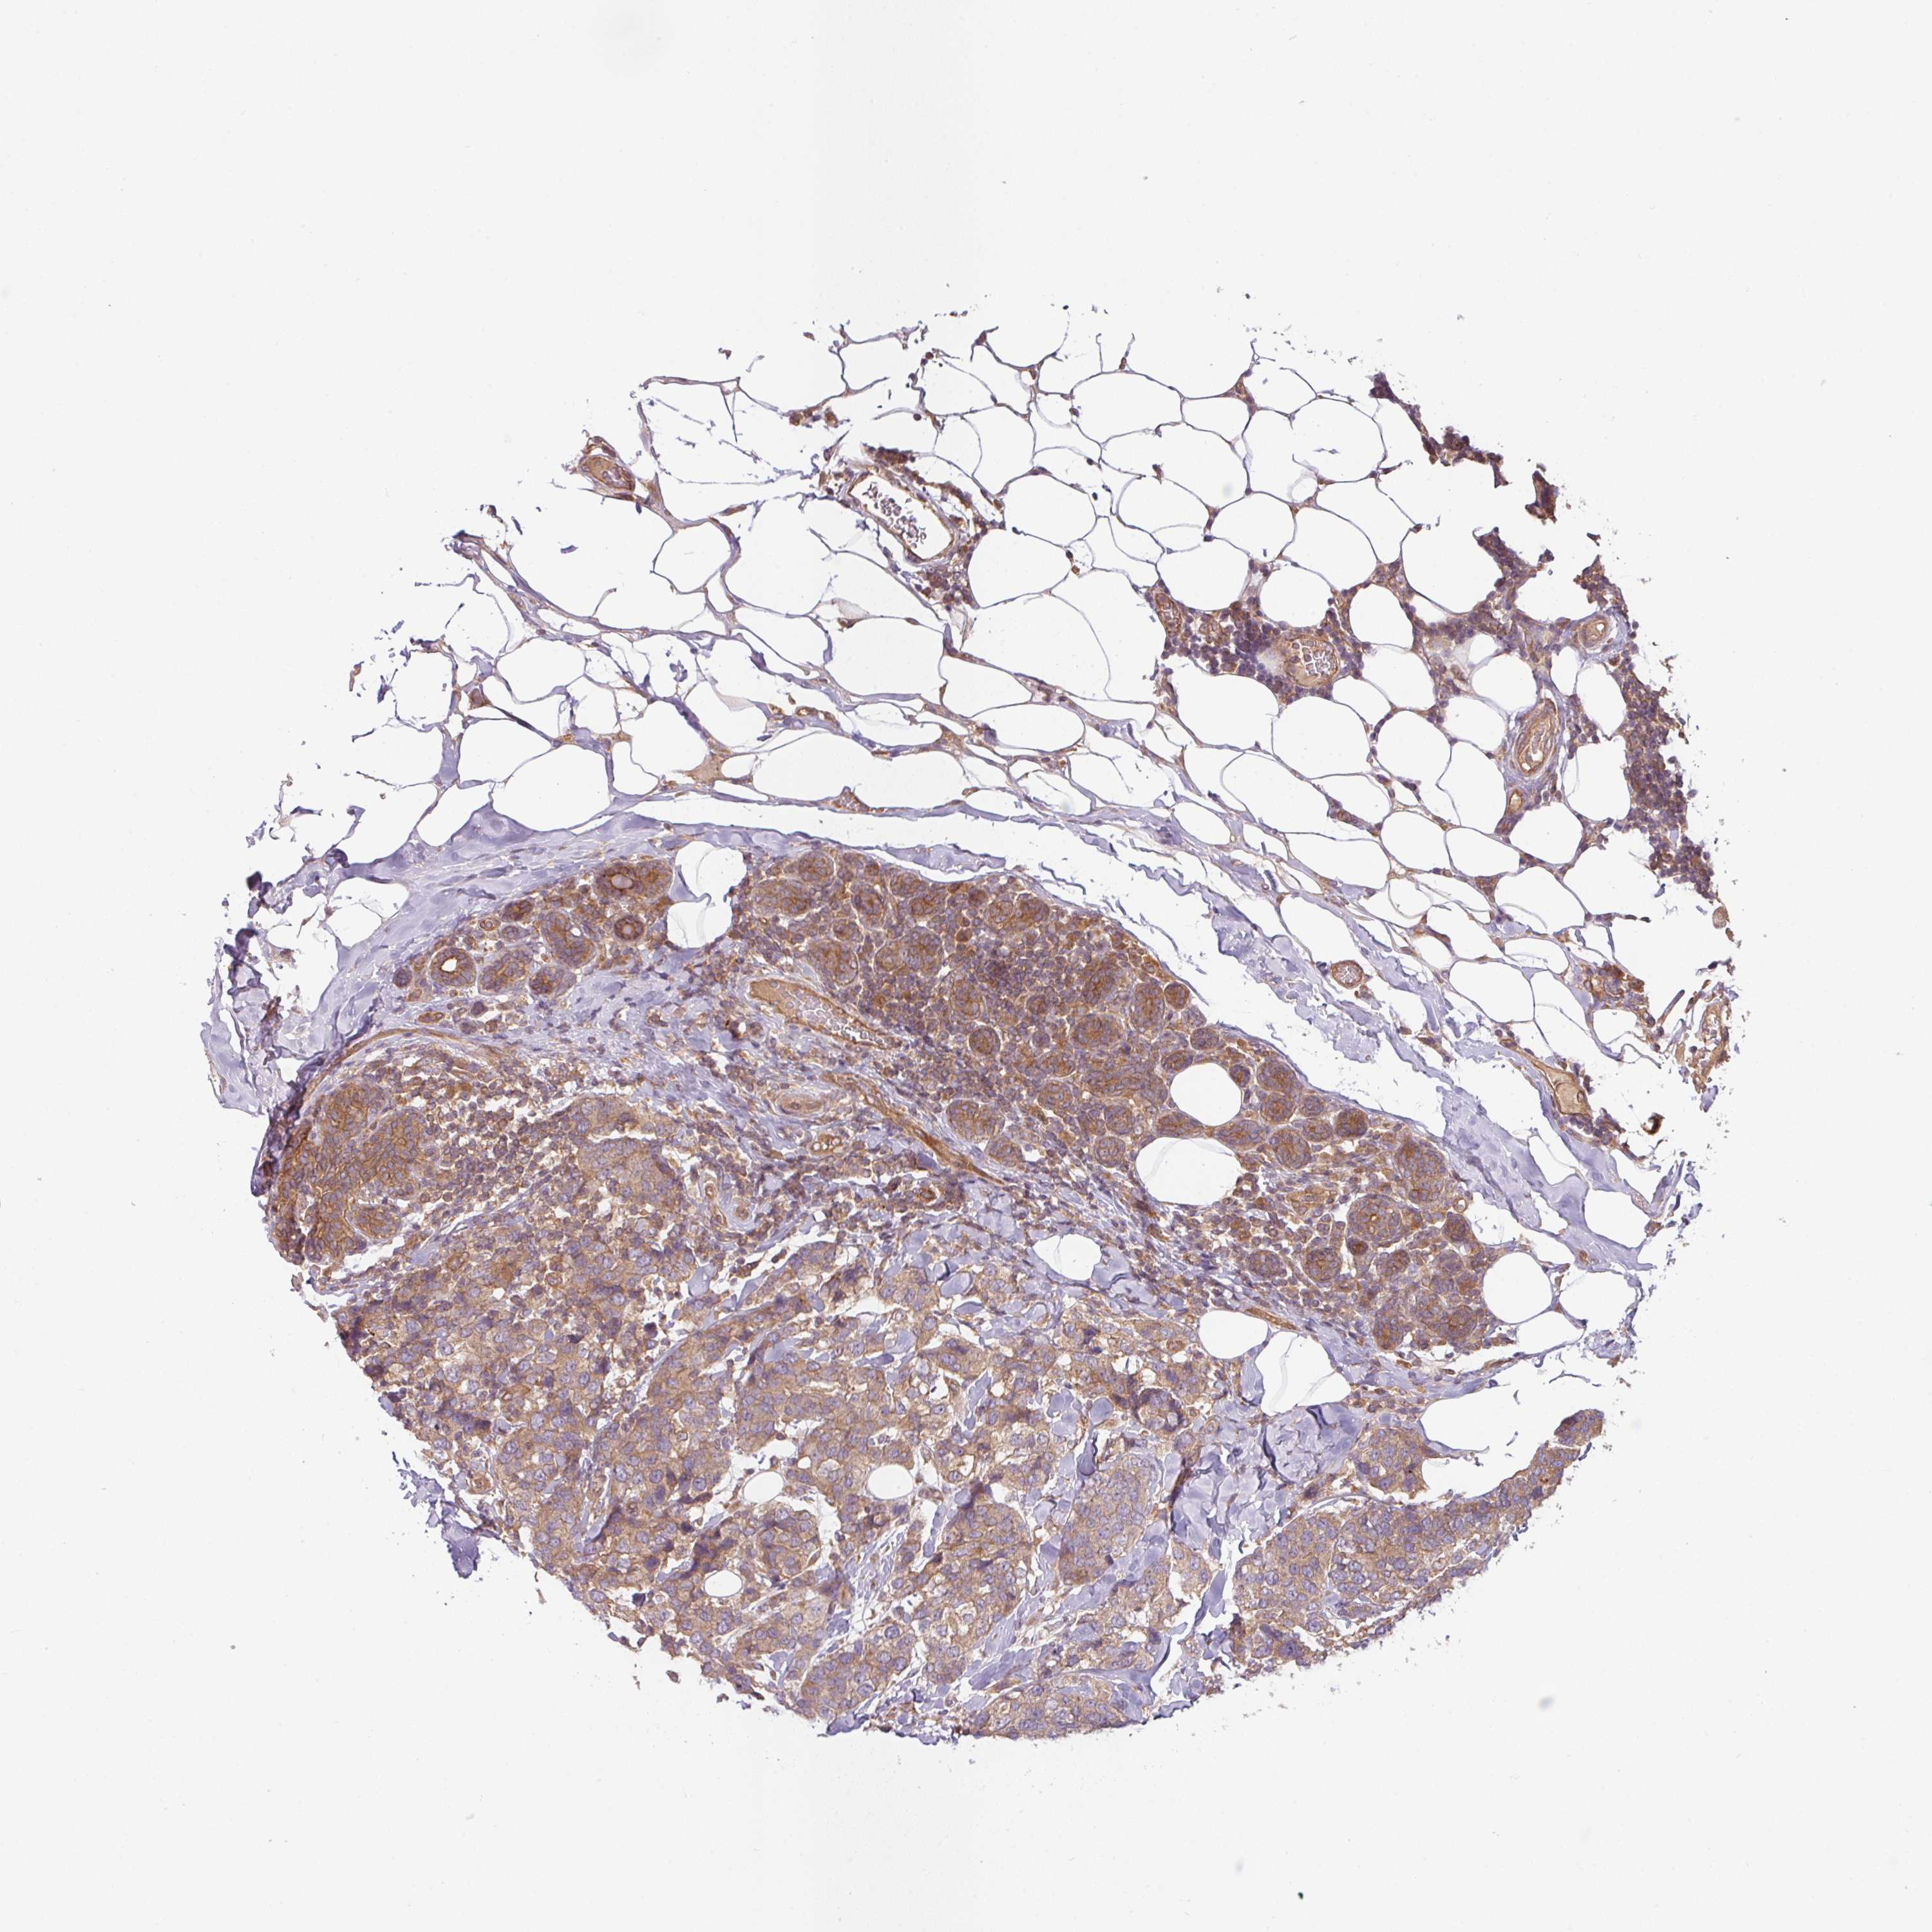

BRCA TCGA BRCA VALIDATION PROTEIN EXPRESSION